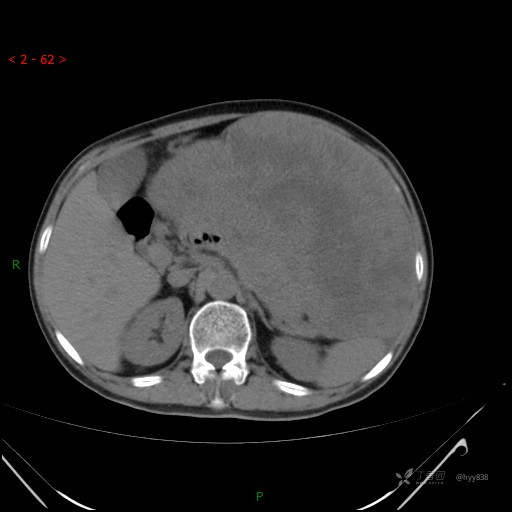

腹部CT平扫